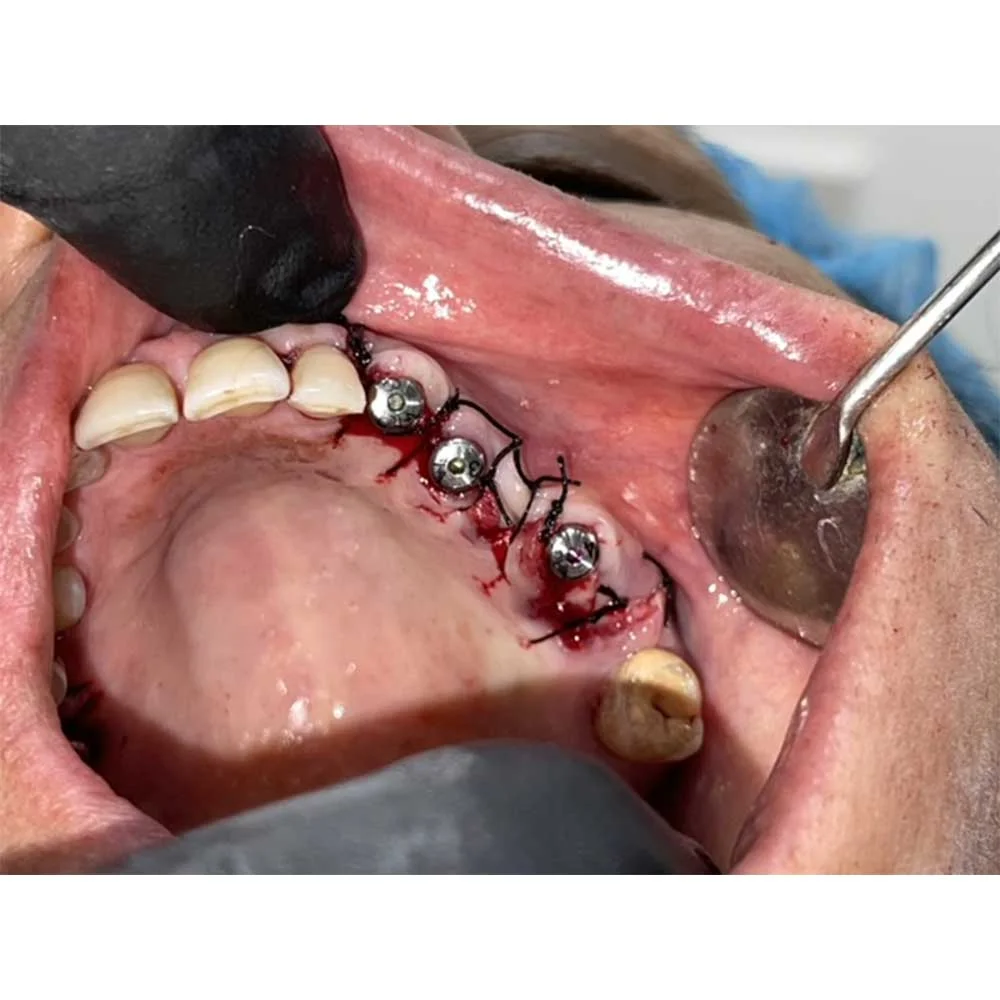

3. All-on-Four Implants: A groundbreaking procedure that uses four implants to rebuild an entire arch.

Full Mouth Implants

Dental Implants